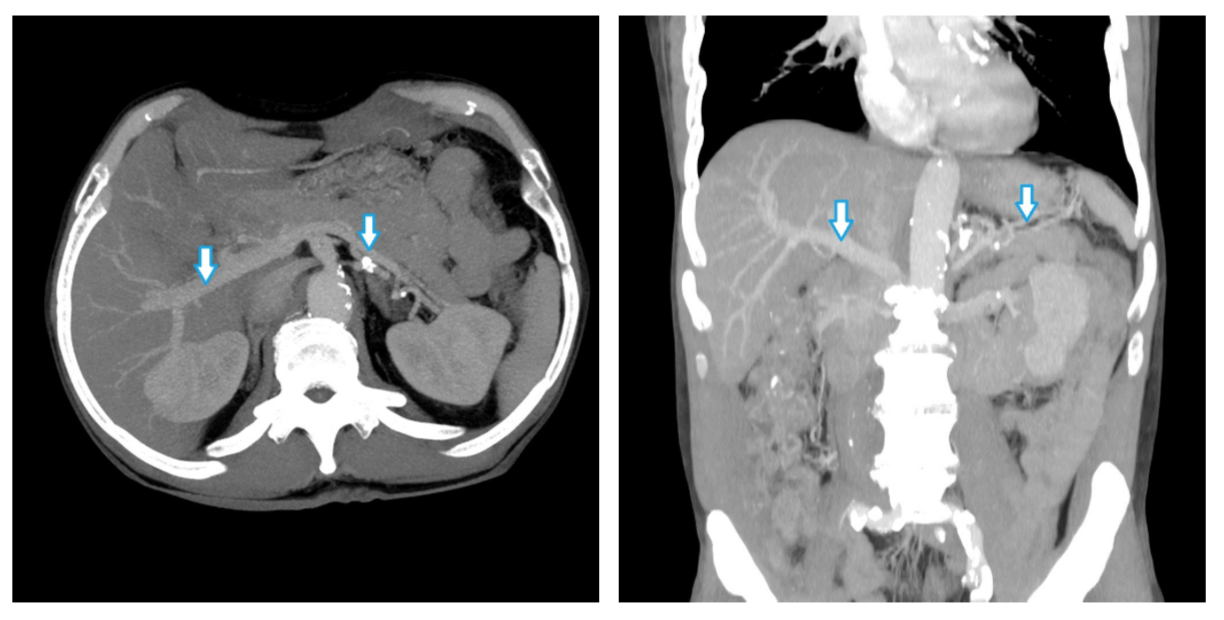

Селезеночный индекс на кт 104 фотографий